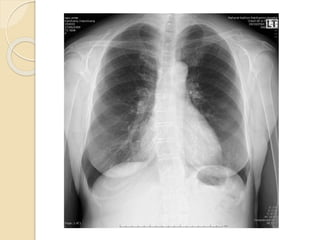

 Film Lt shoulder AP

Investigation

 Film Shouler AP

1. Greater tuberosity 2. Lessor tuberosity 3. Coracoid process 4. Acromioclavicular

joint 5. ส่วนที่ซ้อนทับกันของกระดูก glenoid กับหัวของกระดูก humerus

Investigation  Film ShoulerAP 1. Greater tuberosity 2. Lessor tuberosity 3. Coracoid process 4. Acromioclavicular joint 5. ส่วนที่ซ้อนทับกันของกระดูก glenoid กับหัวของกระดูก humerus